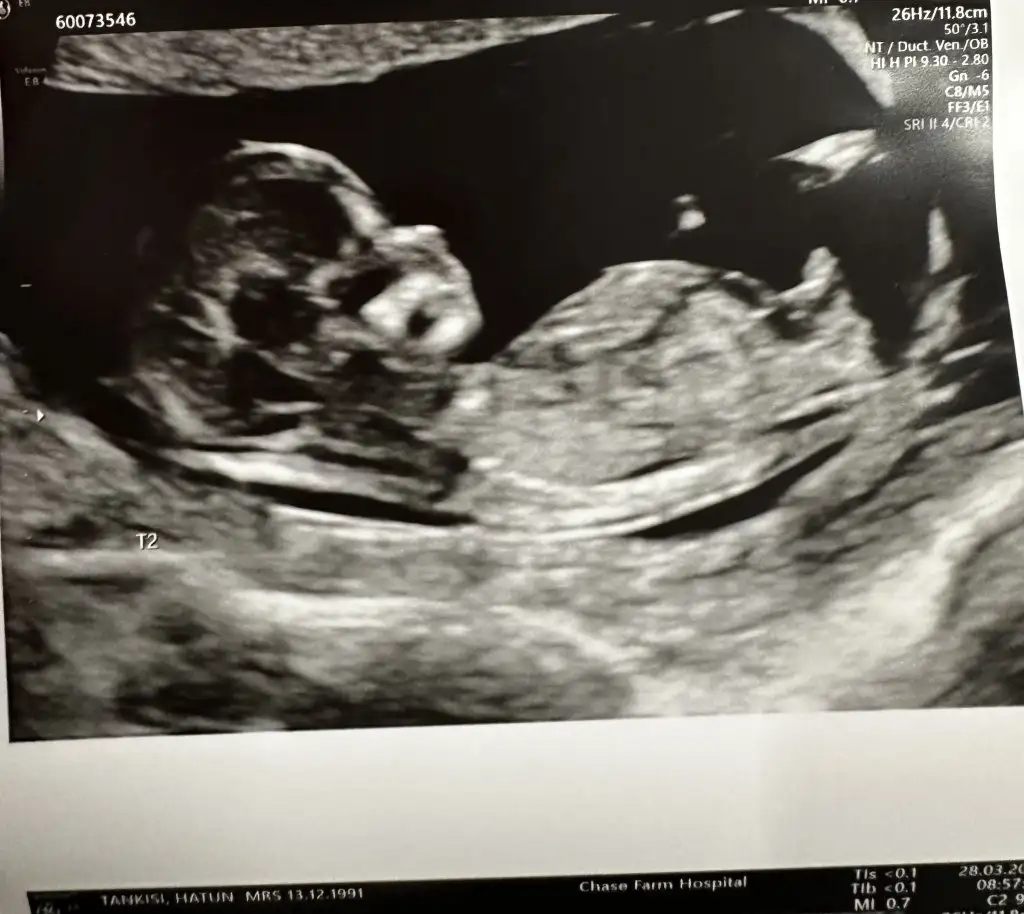

Seni de doktor benim gibi 3 haftada bir çağırıyor. Herkesi 4 haftada bir çağırmış. Muhtemelen ikimizin de daha önce benzer bi kaybı olduğu için. İnşallah sağ salim alırız hepimiz bebişleri kucağımızaMerhaba kızlar ben çıktım doktordan. Önceki gebeliğimde bebeğin kalbi durmuştu 7+3'te. Bunda da 6+1de duymuştuk kalbini aradan 3 hafta geçmişti. Doktor karından baktı göremedi kalp atışını. Ben yıkıldım o an. Alttan bakalım hazırlan dedi. Tabi ben mahvoldum daha önce de bildiğim için süreci. Alttan bakınca duyuldu kalbiömrümden 5 10 yıl gitti resmen nasıl ağladım nasıl. Doktor sarıldı mutlu ol bebek iyi dedi. İletişimi güzel bir doktor sağ olsun. Ölçümde 9+2 çıktı. 3 hafta sonra gel, eğer iyi hissetmezsen daha erken de gelebilirsin dedi. Doktordan çıktım ya sanki üstümden TIR geçmiş gibi nasıl yorgunluk var anlatamam. Allah kimseyi korktuğunda uğratmasın inşallah